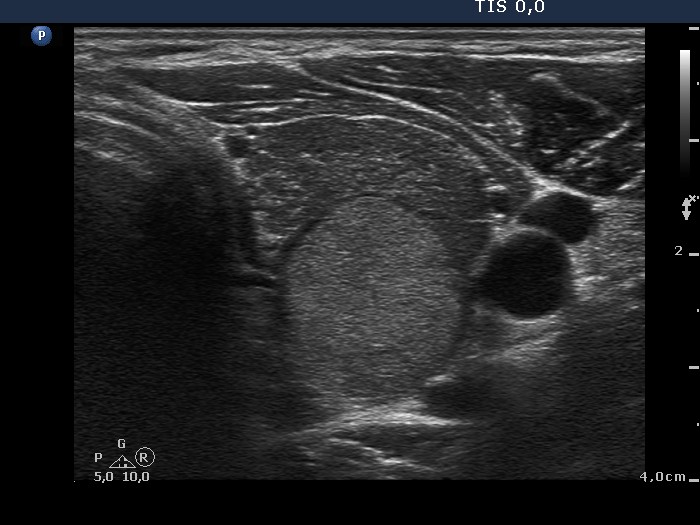

Ultrasonography. A diffusely hypoechogenic thyroid was found with extensive fibrosis. There was an echonormal nodule in the upper dorsal part of the left lobe. The nodule showed taller-than-wide shape and halo sign while the presence of perinodular blood flow was equivocal.

2. Malignancy occurs only exceptionally in an echonormal nodule except for autoimmune thyroid disorders. We must be aware that the echo structure of a nodule may be influenced by the echo structure of the non-nodular thyroid. Therefore, echonormal nodules are targets of cytological investigation in hypoechogenic thyroids, i.e. Graves' disease and in Hashimoto's thyroiditis.

3. The presence of perinodular blood flow is doubtful because the nodule is avascular while the vascularization of the extranodular part is extremely increased. Nevertheless, the nodule proved to be encapsulated on histopathology.

6. The histogram value of the nodule proved to be 74.8, a value which is less than the average of the normal parenchyma, therefore in absolute sense, this is a minimally hypoechoic nodule. In relative sense, compared to the non-nodular part of the particular case, the nodule is hyperechoic.